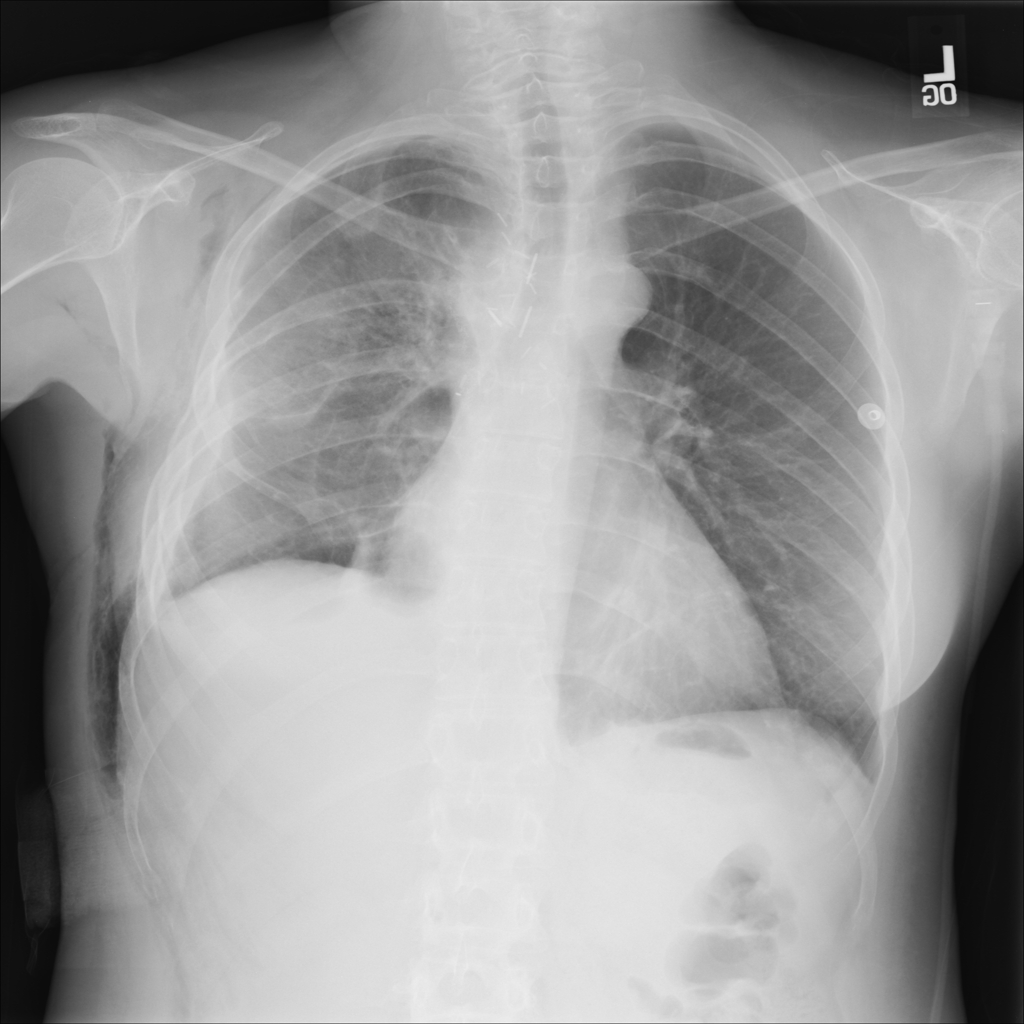

COPD / Emphysema

COPD and emphysema are chronic lung diseases that can change chest X-ray appearance but are not diagnosed by X-ray alone.

Showing up to 90 reference images for Emphysema.